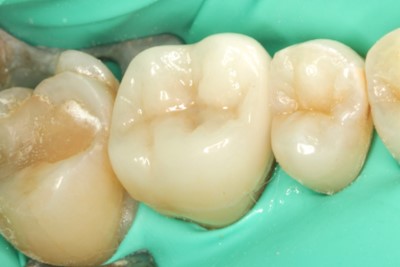

• 治療前

• 治療後